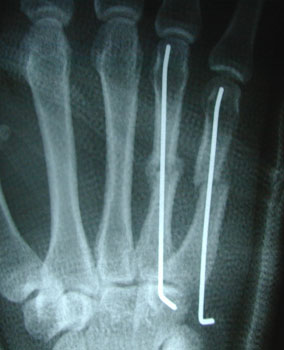

Surgery for metacarpal fractures.

This can be done under a local anaesthetic/ nerve block or general anaesthetic. The fracture is reduced back into the right position and a wire is inserted up the middle of the bone. This acts like an internal splint, holding the fracture in an acceptable position while it heals. If there is rotation of the finger other wires may be inserted across the hand. These wires stay in place for 4 weeks.